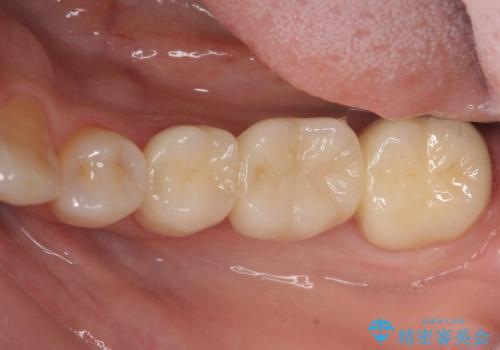

抜歯後の補綴 セラミックブリッジ治療

前後の歯も一緒に審美性を回復することができ、喜んでいただくことができました。